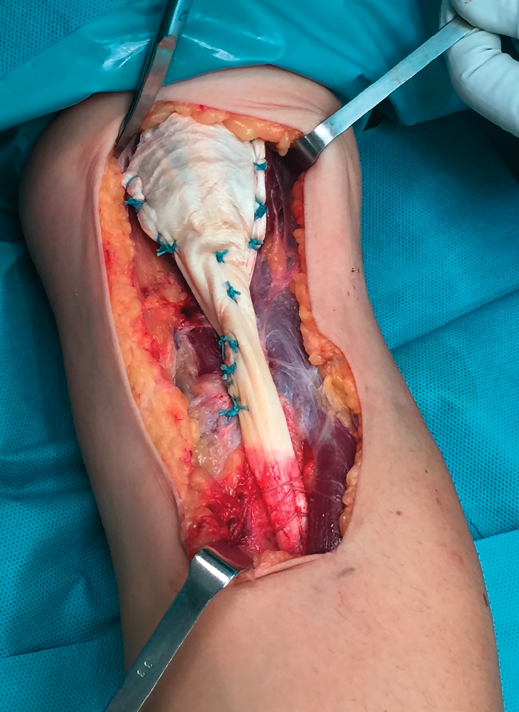

Figura 2. Imagen de la sutura distal del injerto.

La técnica de sutura del injerto de Aquiles fue la de tipo FiberLoop distalmente y anclamos el tendón mediante un botón cortical (EndoButton®, Smith & Nephew) en disposición intramedular en la tuberosidad bicipital del radio para evitar el riesgo de lesión del nervio radial. La sutura proximal fue mediante puntos de tipo Krakow intentando envolver el muñón muscular en toda su circunferencia utilizando la parte proximal del tendón de Aquiles como un abanico desplegado (Figuras 2 y 3).